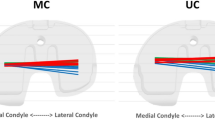

Under weight-bearing conditions for flexion from the extended position, the medial condyle remained motionless. However, the lateral condyle moved 6.0 mm posteriorly from 0° to 100° of knee flexion for the normal alignment group and 9.2 mm posteriorly from 0° to 90° of knee flexion for the varus alignment group. Under weight-bearing conditions, the femoral component displayed a medial pivot pattern.

Under weight-bearing conditions during extension from the flexed position, the medial condyle remained motionless and the lateral condyle moved anteriorly in the normal alignment group and the varus alignment group. Under weight-bearing conditions, the femoral component also displayed a medial pivot pattern.

The most important finding of the present study was that the kinematics were influenced by weight load (weigh-bearing condition) and the postoperative alignment. High weight loading induced a more posterior position. Under weight-bearing conditions, the varus alignment group showed a more posterior position of the medial condyle and a more anterior position of the lateral condyle than the normal alignment group. In contrast, no significant difference was detected between the normal and varus alignment groups under non-weight-bearing conditions.

Recently, Howell suggested that a slight undercorrection of the deformity was beneficial from functional perspective [19], and Vanlommel reported better clinical and functional outcome score in postoperative mild varus with pre-operative varus knees [36]. We also kept the same idea in mind and started to study midresidual varus deformity with pre-operative varus knees. Screw-home movement was first clearly described by Hallen in 1966. Hallen stated that the medial (internal) rotation of the femur on the tibia on full extension stabilizes the joint [15]. In vivo kinematics on terminal extension from the flex position was also evaluated in this study. Our results revealed that varus alignment induced posterior displacement of the lateral femoral condyle on the tibia and led to external rotation of the femur on full extension. Although this rotation is in the opposite direction as screw-home movement, the lateral femoral condyle mobility might be physiological and lead to better functional condition around full extension.